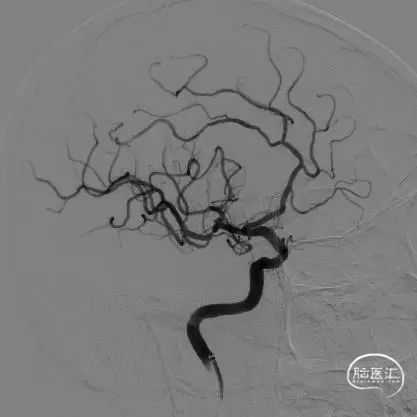

术后影像

术后即刻正侧位造影示:动脉瘤内无造影剂滞留,Raymond分级:3A级。